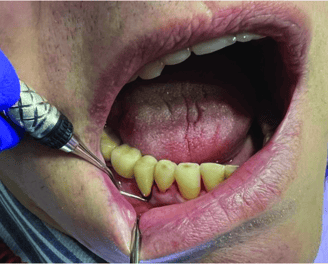

Destartraje supragingival

Consiste en eliminar el sarro y la placa que se acumulan sobre la línea de las encías. Se realiza con instrumentos manuales o ultrasonido para prevenir enfermedades periodontales.

Destartraje subgingival

Se enfoca en la limpieza de debajo de la línea de las encías para eliminar el sarro y la placa que no se puede ver a simple vista. Esto ayuda a reducir la inflamación y la infección de las encías.